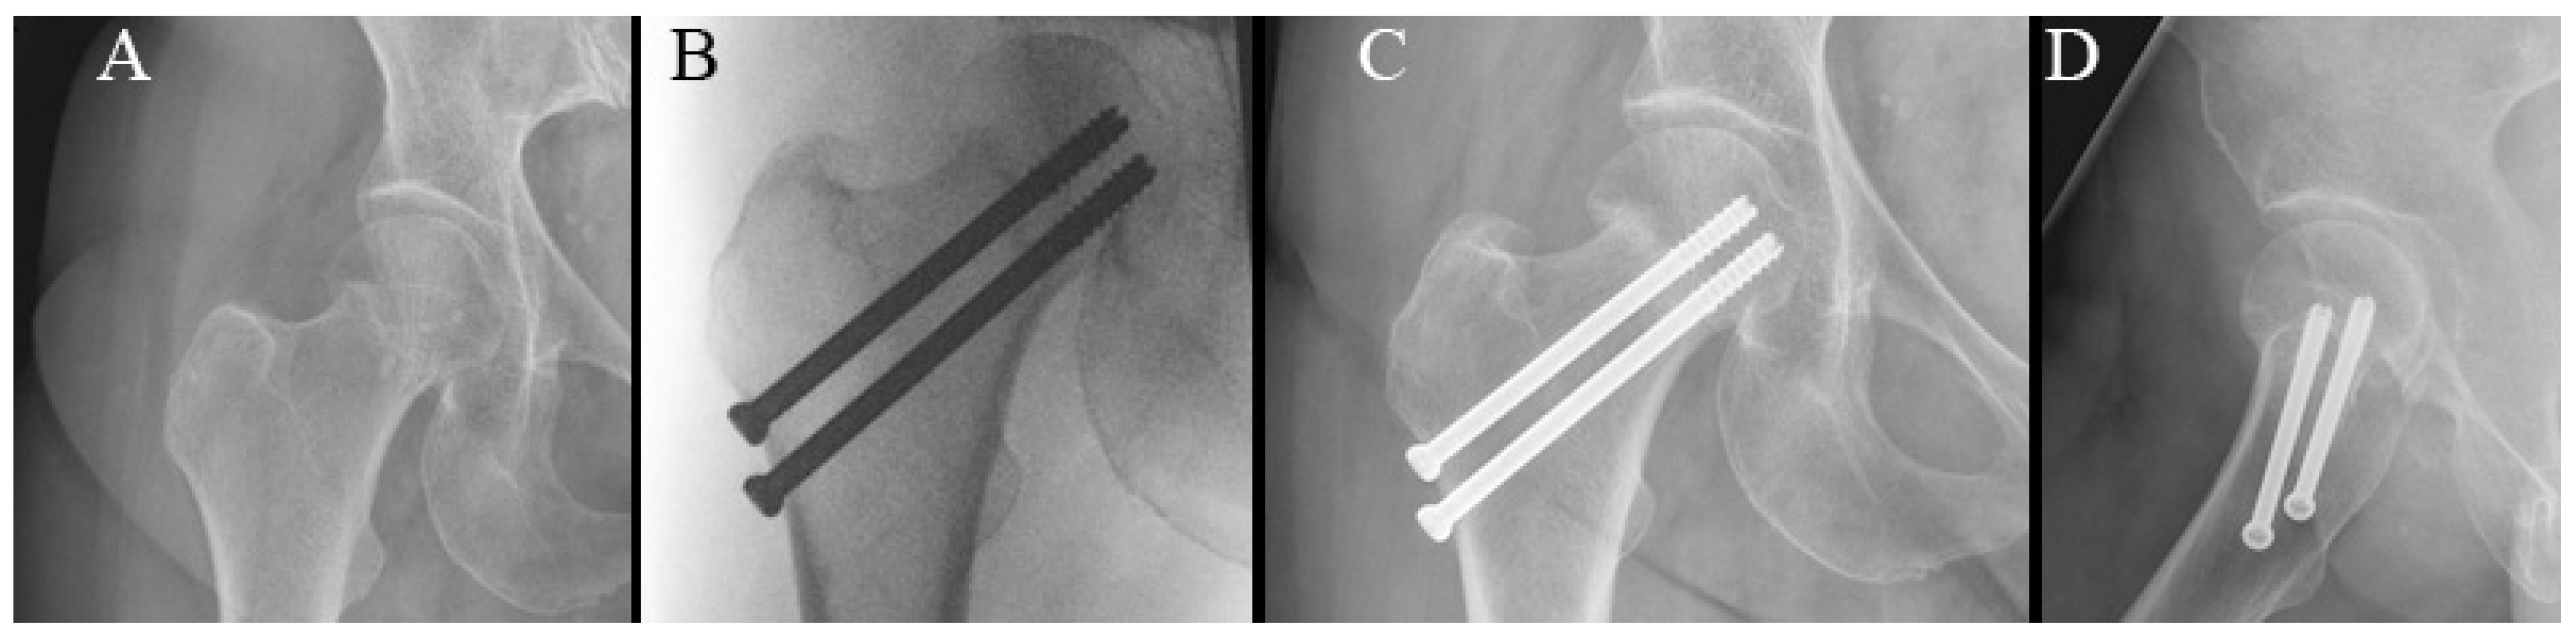

Figure 4.

Radiographs of cannulated hip screw fixation with two screws. (A) Preoperative radiograph. (B) Perioperative radiograph. (C) Anteroposterior radiograph at 6-week follow-up. (D) Lateral radiograph at 6-week follow-up.